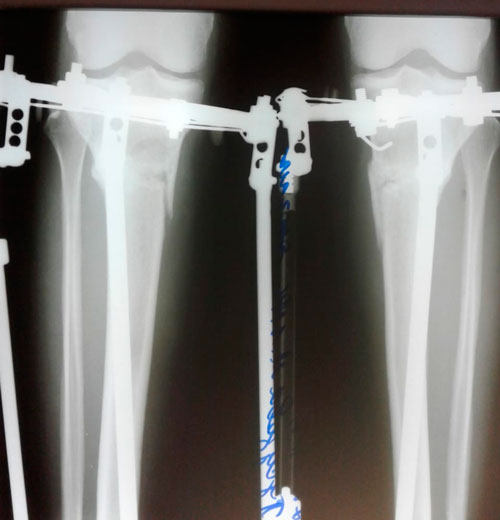

Пациентка - 33 года. Тараз.

Дата операции - 09.01.2019г.

Ротация справа.

Дата снятия аппаратов - 23.04.2019г.

Срок сращения - 101 день.